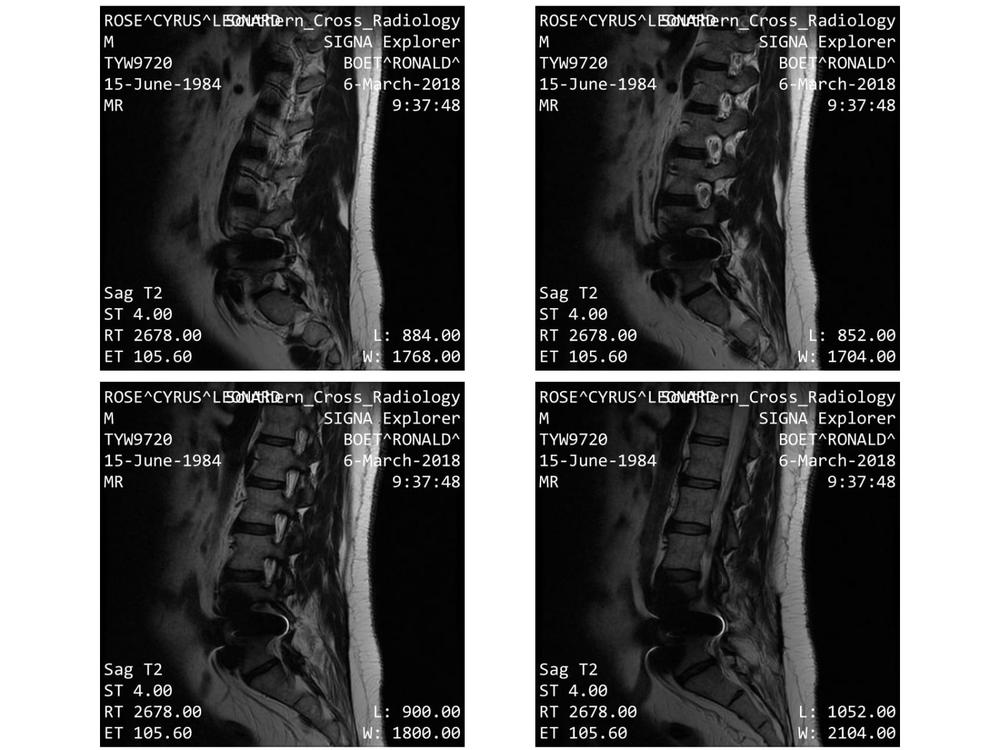

I had artificial discs inserted in 2016 (L4/5 region), but these are causing problems now, and need to be removed. These two, and other adjacent vertebrae, need to be fused in order to alleviate the excruciating pain.

Various orthopedic specialists have worked with me over recent years, including the surgeon who did the operation in Christchurch. But after examining various scans to examine the condition of my spine one of them, an orthopedic consultant Mr Insull, said he could not say with certainty that my worsening condition could be put down a particular incident or incidents. In his opinion it has been a case of a slowly deteriorating spinal condition and so the ACC decided to decline funding for surgery. of course, is sure the worsened condition has resulted from the December 2017 fall while dodging the swerving vehicle as I was fine up until Dec 2017.

In a state of severe, on-going pain, and the maximum allowable dosage of pain suppressing medication does little to relieve the constant agony. I'm confined to bed most of the time, and need assistance to get out bed for toileting, and uses crutches or worker with great difficulty when I attending appointments with the medical specialists. It now seems that the only solution is for the fusion of up to 8 vertebrae to take the pressure off the nerves causing the pain. I managed to keep going until now living with the hope that the next appointment will enable me to have the surgery I desperately needs. Now that I has been declined by the ACC this hope has been dashed.